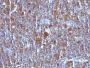

Jurkat, K562, HL-60, or HeLa Cells. Reed-Sternberg cells in Hodgkin's lymphoma.

Flow, intracellular (verified)|IHC, FFPE (verified)

Flow (intracellular) (verified)|IHC (FFPE) (verified)

Higher concentration may be required for direct detection using primary antibody conjugates than for indirect detection with secondary antibody|Immunofluorescence: 1-2 ug/mL|Does not react with mouse or rat, others not known|Immunohistology formalin-fixed 0.5-1 ug/mL|Staining of formalin-fixed tissues requires boiling tissue sections in 10 mM Tris with 1 mM EDTA, pH 9.0, for 10-20 min followed by cooling at RT for 20 minutes|Flow Cytometry 0.5-1 ug/million cells/0.1 mL|Western blotting 0.5-1 ug/mL|Optimal dilution for a specific application should be determined by user